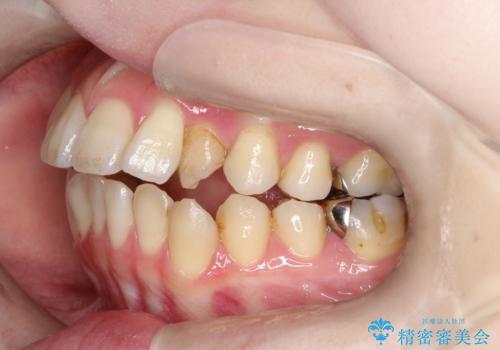

- 開咬と歯のデコボコ(叢生)、八重歯を主訴にご来院された患者様です。

矯正の精密検査の結果、上顎左右4番および下顎左右5番の計4本を抜歯し、ワイヤー矯正(クリア装置)にて治療を行いました。

虫歯があったので、虫歯治療は矯正前に行っています。